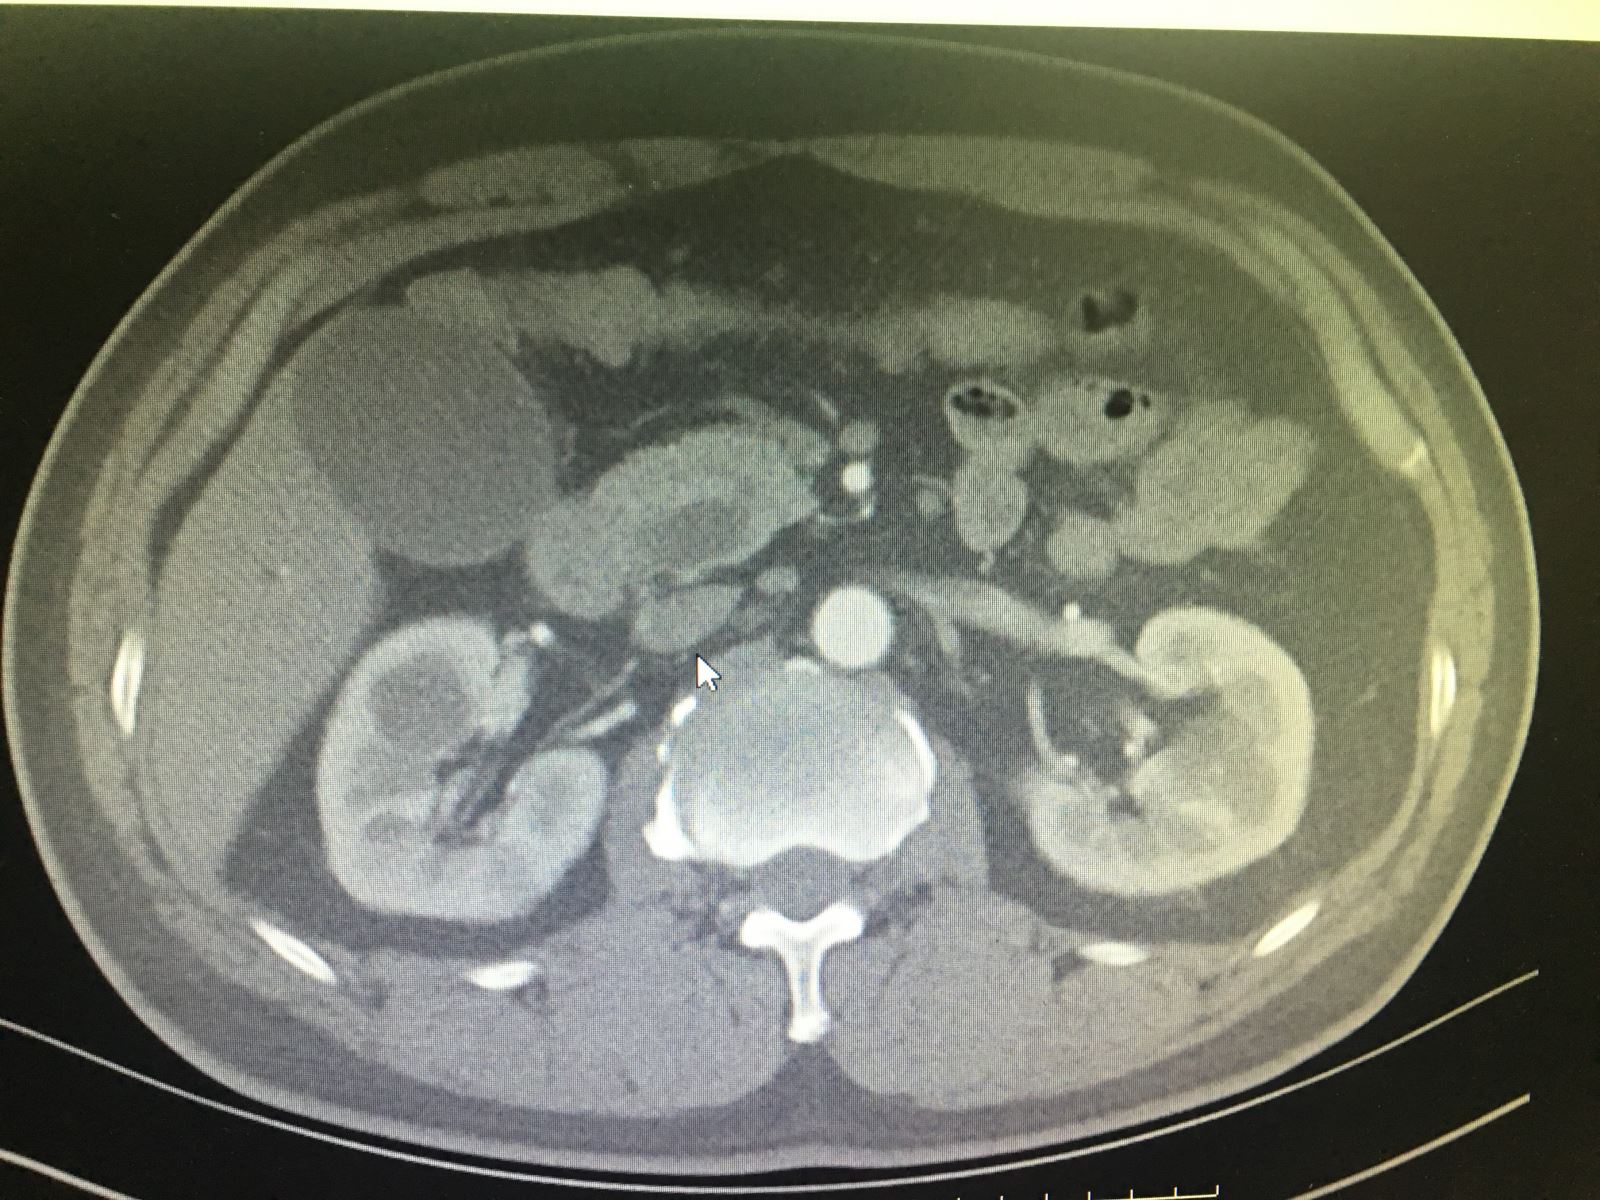

患者徐某,男性,51岁,该患者于3个月前无明显诱因出现巩膜黄染,当时症状较轻,一直未在意,未予诊治。3个月来该患者巩膜呈进行性加重,于半个月前出现全身皮肤黄染,伴瘙痒,尿色加深,呈浓茶水色。期间,曾自行口服保肝药物治疗后,症状并无缓解,于本月14日就诊于通辽市传染病医院,被该院诊断为黄疸待查,建议到我院进行进一步诊治,故次日来我院门诊就诊,以“梗阻性黄疸”收入肝胆胰外科。

入院后,通过腹部彩超、腹部增强CT、胰腺核磁增强及MRCP,血常规、肝功能、肿瘤标记物等相关检查,结合检查结果,该患者胆红素升高、肿瘤标记物升高及相关影像资料,该名患者被确诊为壶腹周围癌。与患者及家属进行充分沟通后,由肝胆胰外科主任医师祁向军主任主刀,副主任医师郭雅明医生、副主任医师邵志远医生协助共同完成,采取吉大一院刘亚辉教授的结肠后入路,钩突先行的方法及洪氏一针法胰肠吻合,顺利为患者在全麻下行腹腔镜胰十二指肠切除术。该手术成功为患者切除病灶,术后给予患者抗炎、补液、保肝等后续治疗,目前该患者各项指标稳定。